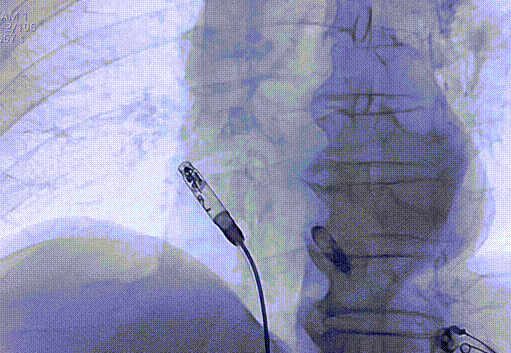

通过股静脉穿刺,建立血管通路,经导丝送入猪尾导管至右心房,分别在RAO 30°和LAO 30°进行右心耳造影,确认目标位置。

右心耳LAO造影

右心耳RAO造影